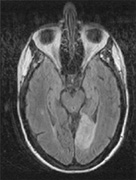

Fig. 18. Magnetic resonance imaging scan of patient with stroke causing a right hemiachromatopsia as well as partial superior quadrantanopia.